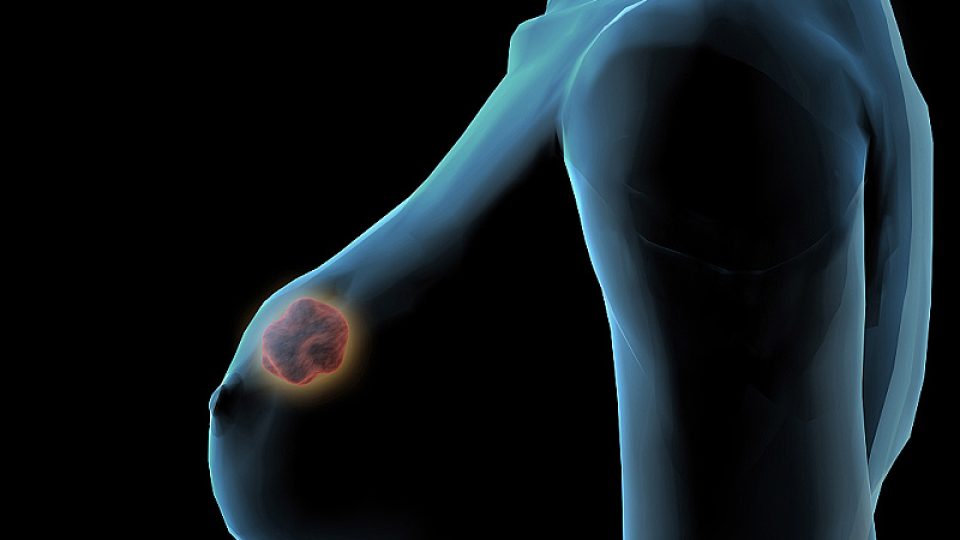

VIDEO: Samovyšetření prsu sice vypadá kámasútroidně, může vám ale zachránit život!

Zdravotnická poradna: rakovina prsu, host: MUDr. Petra Tesařová z Onkologické kliniky VFN v Praze a 1. LF UK. Moderuje Jiří Holoubek.

Každoročně onemocní rakovinou prsu více než 6000 lidí. Pokud v prsu objevíte něco, co tam nepatří, nepanikařte! Nejdřív zkuste samovyšetření. Návod ve videu.

„Samovyšetření sice vypadá komplikovaně, kámasútroidně. Ale když si na něj zvyknete, je to jako běžné čistění zubů,“ říká Petra Tesařová z Onkologické kliniky VFN v Praze a 1. LF UK.

Musíte přijít včas

„Jsou nádory, které jsou velmi dobře léčitelné, přestože jsou zhoubné. Můžete mít ale i tu smůlu, že sice přijdete včas, ale máte velmi agresivní formu bujení. Tady je problém i v časném stadiu. Hodně záleží na rozsáhlosti nádoru,“ vysvětluje Tesařová.

Pokud nádor objevíte a musíte na operaci, je to vlastně jen kosmetická záležitost, na kterou jednou budete vzpomínat. „Ale když přijde do ordinace žena jen o několik měsíců později, je často už pozdě.“ Hlavně po 50 roku věku.

Návod na samovyšetření prsu. Klikněte na video!

Nádorové ZOO?

Rakovina prsu je vlastně obecné označení, které představuje celou zoologickou zahradu různých nádorů. Mohou mít různý vznik, vývoj a léčbu. „Současná léčba dokáže být pacientovi ušitá přímo na míru,“ dodává onkoložka.

Podle lékařky je nejhorší strach z neznámého. Jakmile ale shromáždíte dostatek informací, zjistíte, že řešení existují a že máte naději na úplné vyléčení. Zhoubné nádorové bujení prsu není jen záležitostí ženského pohlaví, může se objevit i u mužů.